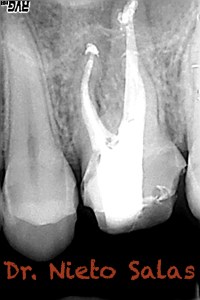

No es habitual en nuestra práctica casos como estos, pero os pongo algunos más:

También, este caso tiene particular interés, porque he conseguido una foto (no sé de donde, perdone al autor), que es muy similar en un diente diafanizado.